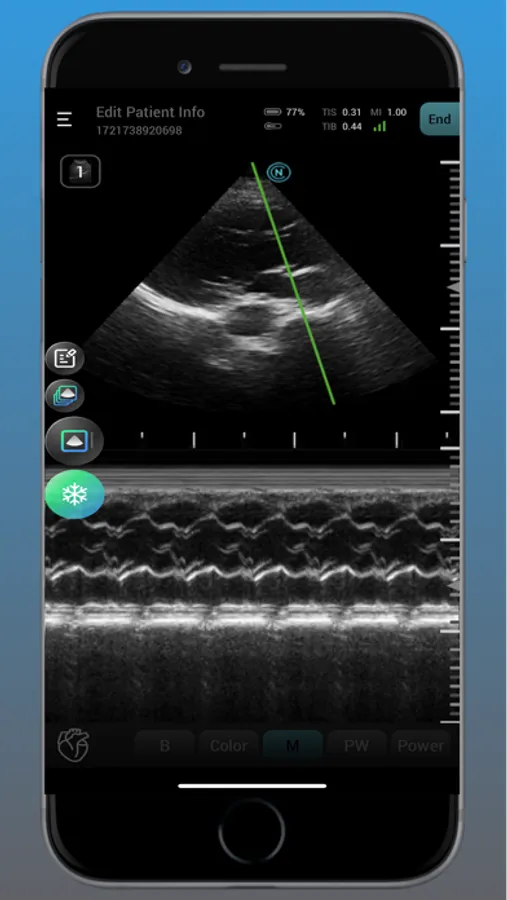

Neo Medical Ultrasound offers high imaging quality in real-time for physicians to improve daily patience care. Neo Medical app features different modes such as B Mode, Color Doppler, Pulsed Wave, and Motion mode. It is designed for medical professionals to easily access user interface to enhance portability and efficiency in daily workflows.

neo Medical Ultrasound System Screenshots